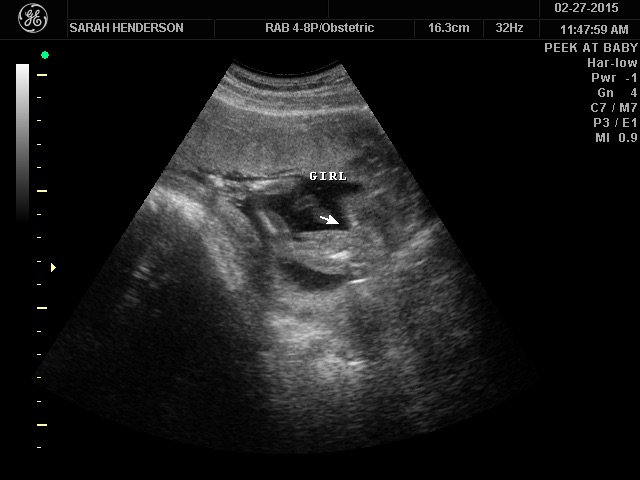

ok so I may be being a bit of an attention whore considering I've posted on two different threads, but I wanted more people to see it.. I found out the gender today, ITS A GIRL!!! I've never felt so happy in my life, it's such an amazing feeling! I've known it was a girl since the day I found out but no one believed me lol.. My beautiful Leighton Skye Henderson! Now I can start shopping & decorate the nursery!

Couple of things, you have your full name, baby's full name and picture of your baby's genitals on the internet. You might want to crop out your name and leave off the picture proving she is girl. Once it's out there who knows what someone might do with the information!